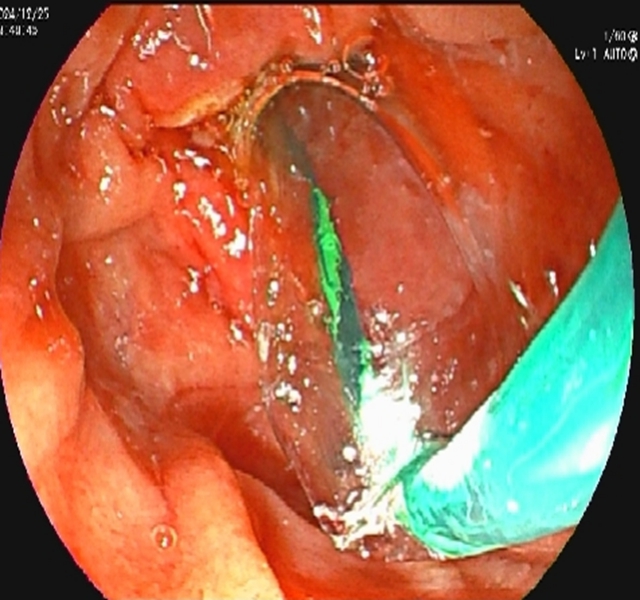

术后,放置鼻胆管持续引流脓性胆汁(当天引出300ml浑浊胆汁)。

4.一举多得:引流+诊断同步完成

内镜逆行胰胆管造影不仅能取石,还能通过鼻胆管持续引流脓性胆汁(每天引出200-500ml),快速降低胆道压力;同时,术中可采集胆汁送细菌培养,指导后续抗生素使用,实现"边治疗边诊断"。